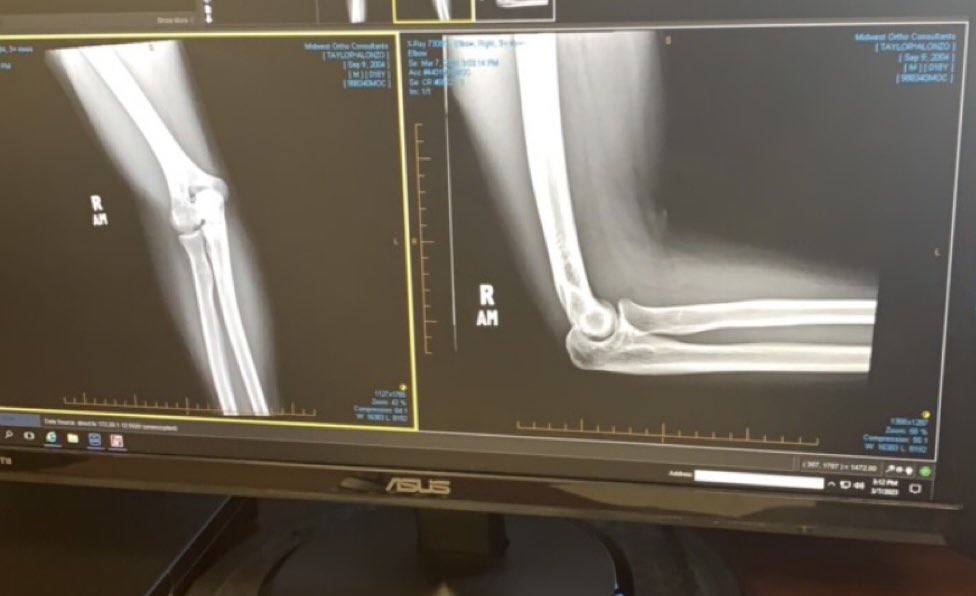

On January 22nd I got shot and my life changed. I want to thank God for sparing me. Minor setback for a Major Comeback!!💪🏾. Doctors cleared me to play. Back In the gym training and recovering look at GOD! Recruitment still open Coaches!!! @247recruiting @CoachBigPete @DeepDishFB